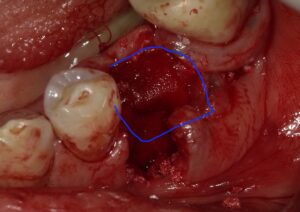

抜歯後インプラントを埋入しましたが骨が足りずネジが

見えています。

人工骨を填入しメンブレンを敷いたところです。